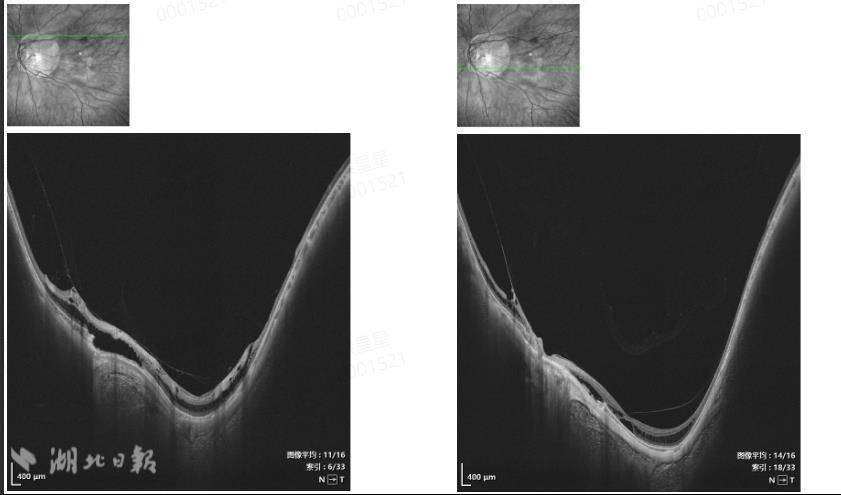

经查,吴先生右眼裸眼视力0.02,戴镜矫正视力为0.5;左眼裸眼视力0.02,戴镜矫正视力却只有0.1。扫频OCT检查进一步显示,他的右眼黄斑部神经上皮层内有低反射暗腔,呈桥样连接;左眼黄斑部网膜表面可见中高反射光带,与网膜呈牵拉状,神经上皮层内及层下见低反射暗腔,部分呈桥样连接。进一步检查确认,吴先生是因高度近视引起的双眼视网膜劈裂症,其左眼病情更为严重,需要手术治疗,而其右眼因为高度近视周边有变性区,需要择期进行预防性激光治疗,以避免进一步进展为视网膜裂孔或视网膜脱落等严重并发症。

患者眼部检查结果。